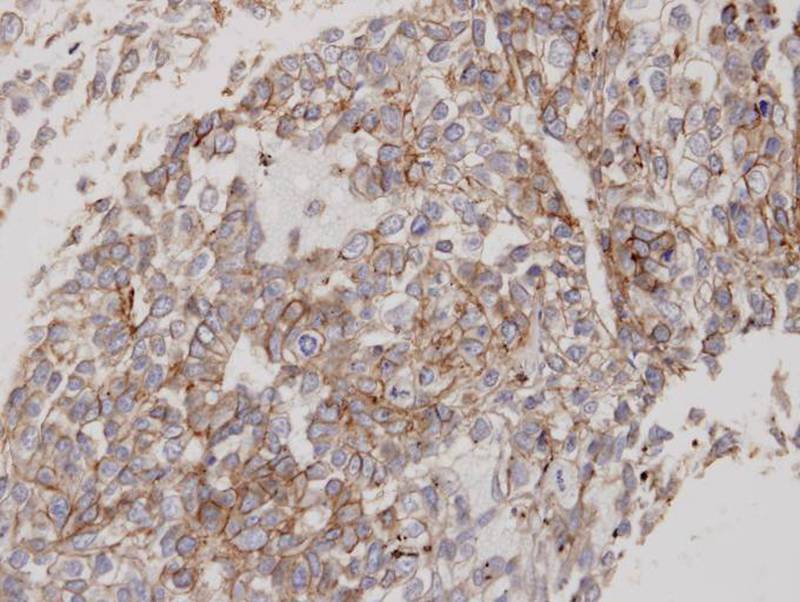

Immunohistochemical analysis of paraffin-embedded Lung CA, using Flotillin-2 antibody at 1: 100 dilution.